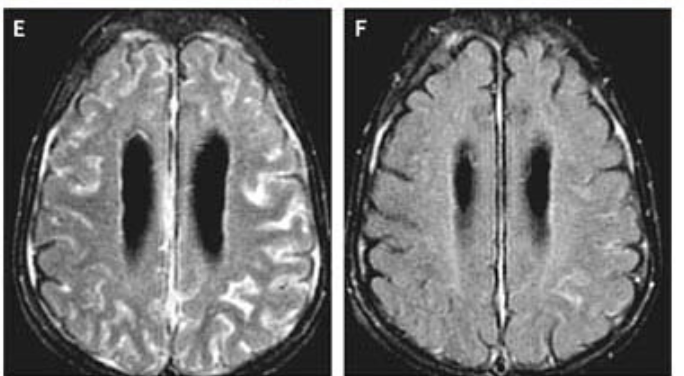

Dr. @emilyliangmd expertly presenting at #ASH25 the largest study to date diving into the use of anakinra for refractory/severe ICANS (n=101). We benchmark key clinical outcomes, and identify potential predictive biomarkers of anakinra efficacy. Prospective comparative studies critically needed! #CARTx #anakinra #CARTOX @OHSUNews